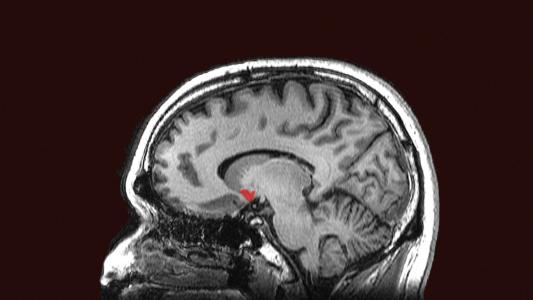

How you breathe affects your brain

A psychiatrist and neuroscientists investigate how breathing affect the brain and biological markers of stress and immune function.

Electrically stimulating the brain helps stop binge eating

Two people with binge eating disorder reported that deep brain stimulation helped them control their eating and lose weight in a small study.

New deep brain stimulator is powered automatically by breathing

A deep brain stimulator powered by breathing could eliminate the need for patients to undergo regular battery-change surgeries.